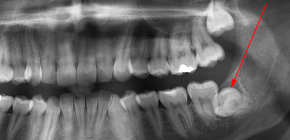

Trattenuto denti del giudizio e la loro rimozione (quando non possono esplodere)

In generale, per qualsiasi motivo, qualsiasi dente può essere ritardato, ma molto spesso stiamo parlando di otto - denti del giudizio. Comunque sia, la ritenzione del dente (cioè la dentizione difficile) spesso causa a una persona problemi molto seri. Sull'esistenza di modi per aiutare il dente retinato a esplodere normalmente senza ricorrere alla rimozione, nonché su come proteggersi dall'infiammazione purulenta e in quali casi è necessario sbarazzarsi del dente il prima possibile - ne parleremo più in dettaglio ...